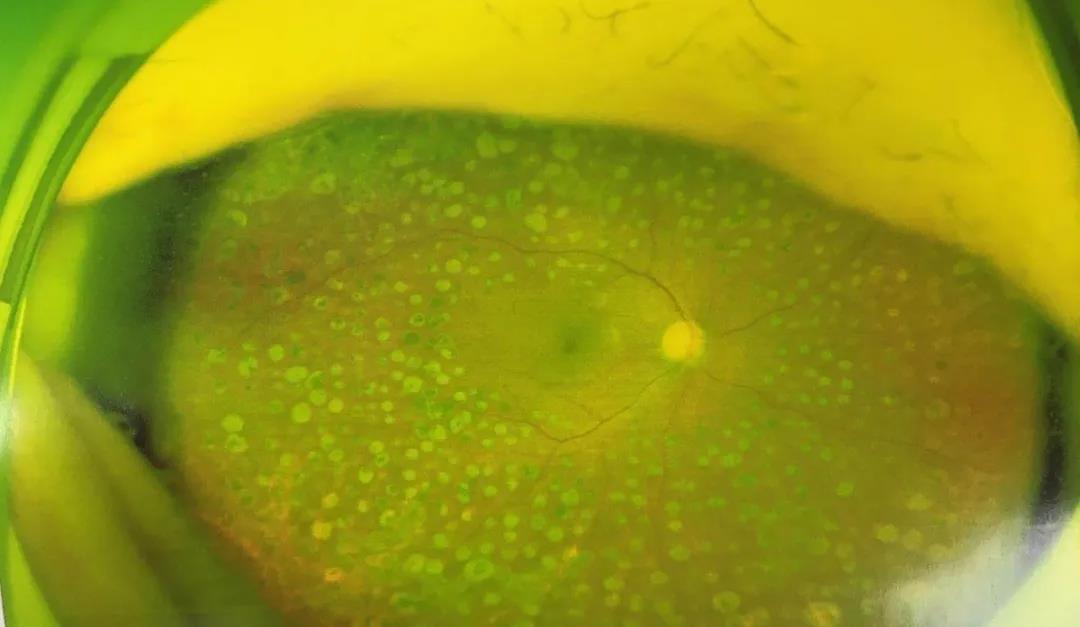

沈阳何氏眼科医院眼底病专家李军院长为赵阿姨做了细致的检查,结果显示为右眼玻璃体积血、双眼增殖性糖尿病视网膜病变以及右眼老年性白内障。

李军院长根据赵阿姨的检查结果,果断为其制定了手术方案,并于3月11日实施了手术。患者术后恢复良好,不仅修复了出血的视网膜,还一并治好了右眼白内障,复查时,右眼视力达到0.8,在视觉质量上得到了很大的提升。

术后眼底对比▼